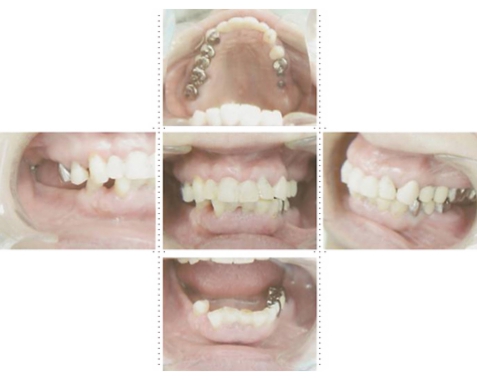

症例2

62才 女性

上顎は総義歯、下顎はブリッジと局部床義歯が装着。義歯は違和感があり、食事も不便を感じ、審美的にも人前にでるのが苦痛に感じていました。この状態を打破するためにも、「インプラント治療に自分の人生を賭けてみたい」という覚悟で来院されました。インプラント手術に対する恐怖心も強くお持ちでした。このような骨幅が狭いケースでは、X線撮影と共にCT撮影による画像診断とインプラント埋入シミュレーションが重要です。

下顎は両側犬歯を残し、他は抜歯。インプラント7本埋入。 上顎はインプラント8本埋入。 インプラント手術を受けられる患者さんは、前の晩眠れない程の不安感、恐怖心を持って来院されます。実際には麻酔注射は痛みを感じず、インプラント手術も痛みも無く、短時間(1本平均3分)で終わるという、当院独自のテクニックにより、2回目からのインプラント手術は気楽になるようです。 前歯は仮歯の段階で患者さん、歯科医、技工士の三者で、審美性・機能性の面から10回以上形態修正を繰り返し検討した後、上・下顎共に前歯・小臼歯はセラミック(MB)クラウン、大臼歯はゴールドクラウンを装着。ご本人とご家族の方にも、「アンチエイジングには、審美インプラント治療が一番効果あり」と大変喜んで頂きました。